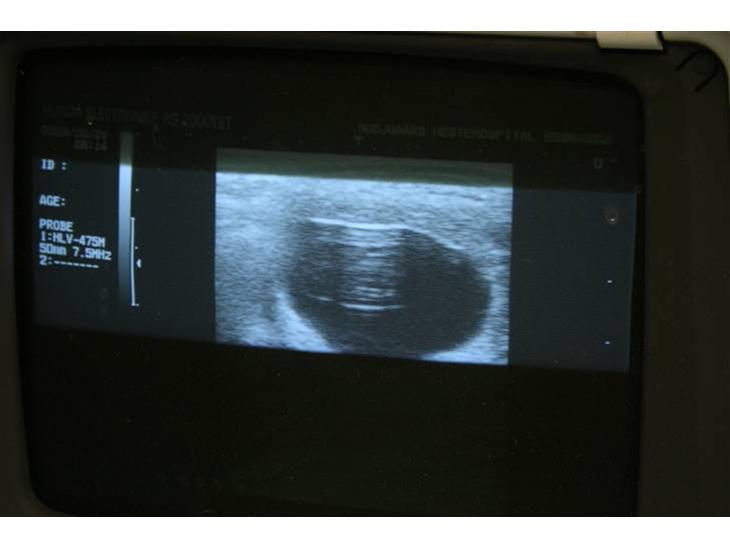

Canna blev insemineret med Onne 376 den 5. juni 2008.. Canna's 325. dag er den 26. april 2009.. 340. dag er den 11. maj..

Dog stødte der komplikationer til allerede den 25. marts 2009.